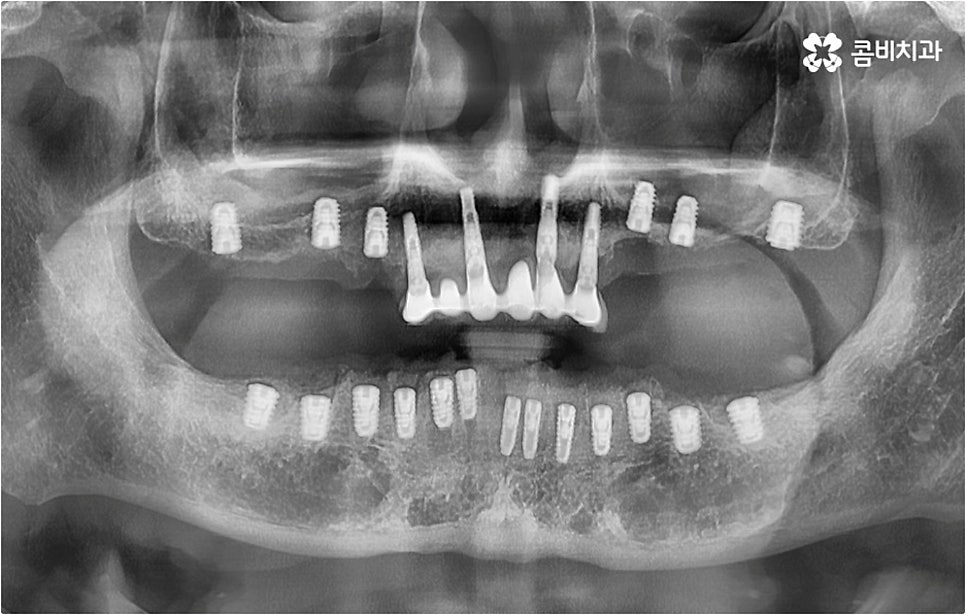

아무 것도 없는 상태에서 제대로 저작 기능을 발휘할 수 있도록 다시 구강 내부를 재현하는 전악임플란트 는 굉장히 고난도에 속하는 치료이기 때문에 충분한 임상 경험을 가지고 있는 숙련된 의료진과 함께 하실 필요가 있어요. 전악임플란트 방식이 빠진 영구치 자리마다 다 임플란트를 식립하는 것이 아니라, 상하악 각각에 8~12개 정도로 필요한 최소한의 인공 치근을 심고 그 사이 사이는 브릿지 방식으로 보철물을 연결하는 것이기 때문에 저작력을 골고루 분담하여 안정적인 지속성을 높일 수 있도록 환자 개개인의 상태에 맞게 인공 치근의 위치, 각도, 간격, 심는 깊이 등을 세밀하게 설정하여 교합을 제대로 맞출 수 있는 시술자의 뛰어난 기술력과 풍부한 노하우가 요구되는 거예요.

또한 이를 위해서 치아 주변 조직과의 거리나 잇몸뼈 높이, 밀도 등을 정확하게 파악할 수 있도록 도와주는 3D CT와 같은 정밀 진단 장비를 갖추고 환자분들의 상황에 맞는 계획을 세워 무리하지 않게 진행할 수 있는 체계적인 시스템을 운용하는 치과에서 임플란트 시술을 받으실 필요가 있어요. 만약 치과내 자체 기공소를 갖추고 있다면 보철물 제작에 대한 피드백이 보다 빠르게 전달, 반영될 수 있어 환자분들이 이용하시기에 좀 더 편안하실 거예요.